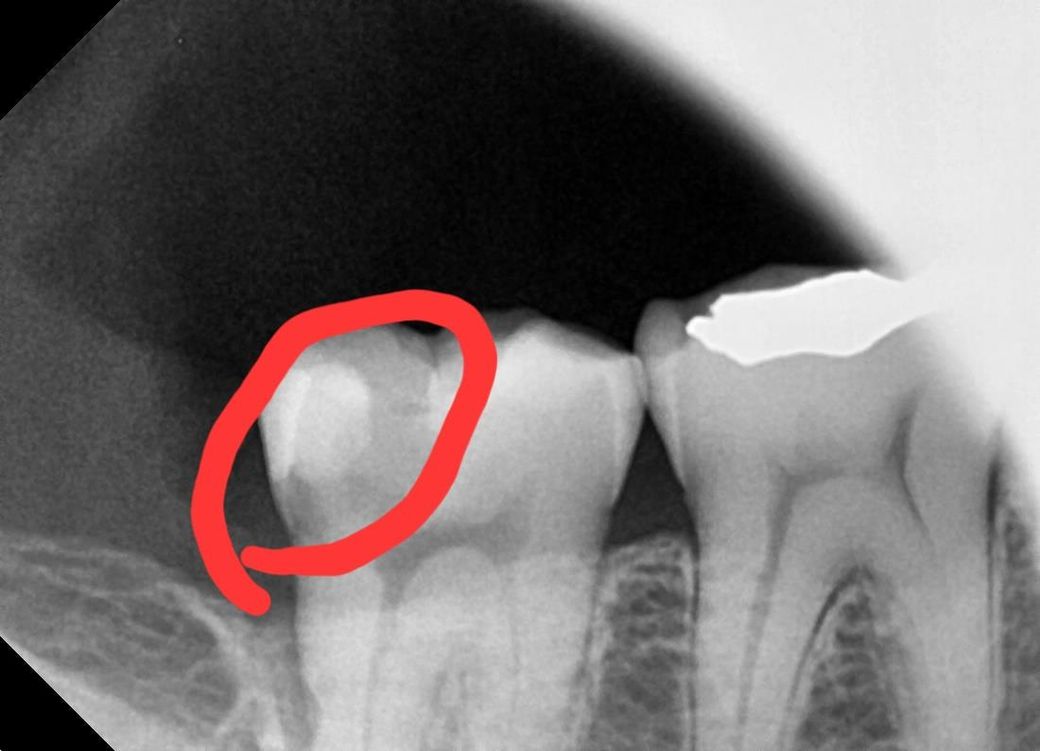

오른쪽 아래 어금니 인레이 깨짐 재치료 문의드려요

제가 약 일년전쯤 오른쪽 아래 어금니를

인레이 치료를 했었는데요

당시에 해당부분 우식이 심해 깊게 파야했고,

당시 선생님 말로는 파보고 신경 닿는부분 까지 진행됐다면 또는 너무 시리다면 신경치료를 하고 크라운을 해야한다고 했습니다

그런데 다행히 파보니 신경까진 닿지 않아서

하이브리드로 인레이 치료 하고 끝냈었는데요(인레이 하기전까지 엄청 시렸음)

해당 인레이가 지난주 목욜 저녁에 피자먹다가 깨져가지고 (전부깨지진않고 끝에서 절반정도 깨진듯 함)ㅜ

예전에 인레이 했던 부위가 너무 넓어서 인레이로 다시 치료해도 또 깨질 확률이 크다며

지르코니아 크라운을 추천하더라고요

근데 저는 만약 인레이로 다시 가능하다면 굳이 생니를 더 자르고 싶진 않아서 인레이로 가능한지 물으니(인레이로 해도 약간 더 깎긴 해야한다고 하심)

할수는있겠지만 어짜피 또 금방 깨질확률이 크기에 크라운을 추천한다고 하시더라고요

• 1번 째 사진